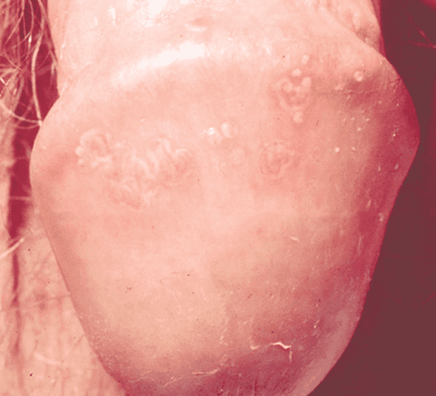

Human Papillomavirus (HPV) in Men

HPV symptoms in men include warts on your penis, scrotum, and/or anus.

The small bumps or group of bumps appear small or large, risen or flat, and can be shaped as a cauliflower. Warts rarely cause pain or discomfort, though they may feel itchy or tender.